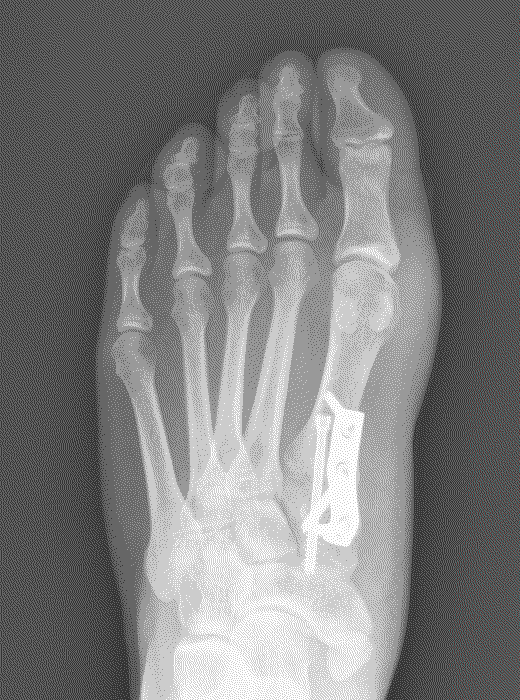

The severity of the condition is assessed by an X-ray. There is no direct correlation between the size of the deformity and the degree of symptoms experienced.

Lapidus (metatarsal cuneiform fusion)

This involves a fusion of the first metatarsal cuneiform joint, allowing the first metatarsal to be rotated back into a straight position. It is normally reserved for severe deformities. Once the corrected position has been obtained it is usually maintained with a plate and screws.

Possible risks with a Lapidus

Due to the corrective power of this procedure, there is a risk of overcorrection of the bunion, which may result in poor alignment with associated pain and arthritis in the big toe joint. A failure of the two bones to unite (non-union) can result in poor alignment and pain. In our department the audited risk of a non-union is 2%, which is lower than the average reported rate of 3.8%. A non-union may require revision surgery.